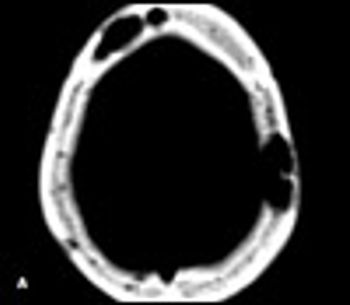

A39-year-old man with a history of AIDS and nonadherence to highly active antiretroviral therapy (HAART) presented with frontal headache and scalp pain of 2 weeks' duration. These symptoms were accompanied by nausea, weight loss, and generalized weakness. Physical examination revealed a small, tender scalp lump, 2 × 2 cm over the left parietal area. The findings from the rest of the examination were unremarkable.